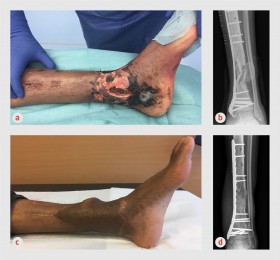

Op 20 februari is de nieuwe richtlijn fractuur-gerelateerde infecties gepubliceerd. Aan deze richtlijn, geinitieerd door de Nederlandse Vereniging voor Heelkunde hebben (trauma)chirurgen, orthopeden, internist-infectiologen, plastisch chirurgen, artsen-microbioloog en radiologen meegeschreven. De bestaande evidence wordt samengevat en een praktisch schema geeft de clinicus handvatten om deze complexe infecties met geinfecteerd kunstmateriaal goed te behandelen.